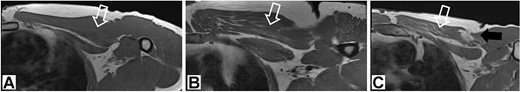

In this study, we presented a prospective comparative study of 40 patients underwent anatomical reconstruction of the PMM tendon using autologous fascia lata graft or autologous hamstring graft [15, 16, 22]. All patients have presented chronically ruptured muscles (Fig. 1) and were evaluated with MRI (Fig. 2) before the surgery. All patients underwent histological evaluation of the pectoralis tendon in a biopsy took during the repair surgery (Fig. 3).

1.5 T T1 magnetic resonance image showing chronic aspects within the pectoralis major muscle.

Magnetic resonance image of the affected muscle

We performed MRI image analysis in 20 patients underwent surgical treatment. Those patients were randomized from all surgical patients in a ration of 2:1 with 10 non-weightlifting athletes’ controls. We used MRI to assess muscle degeneration prior to surgery using a protocol designed for PMM evaluations. For this randomization we used randomizer.org in a simple way. All patients evaluated with MRI had histological evaluation also. All MRI were performed using the same 1.5 T MRI machine (Siemens, Erlangen, Germany); the parameters are provided in Table 1 and degeneration evaluation in Table 2.